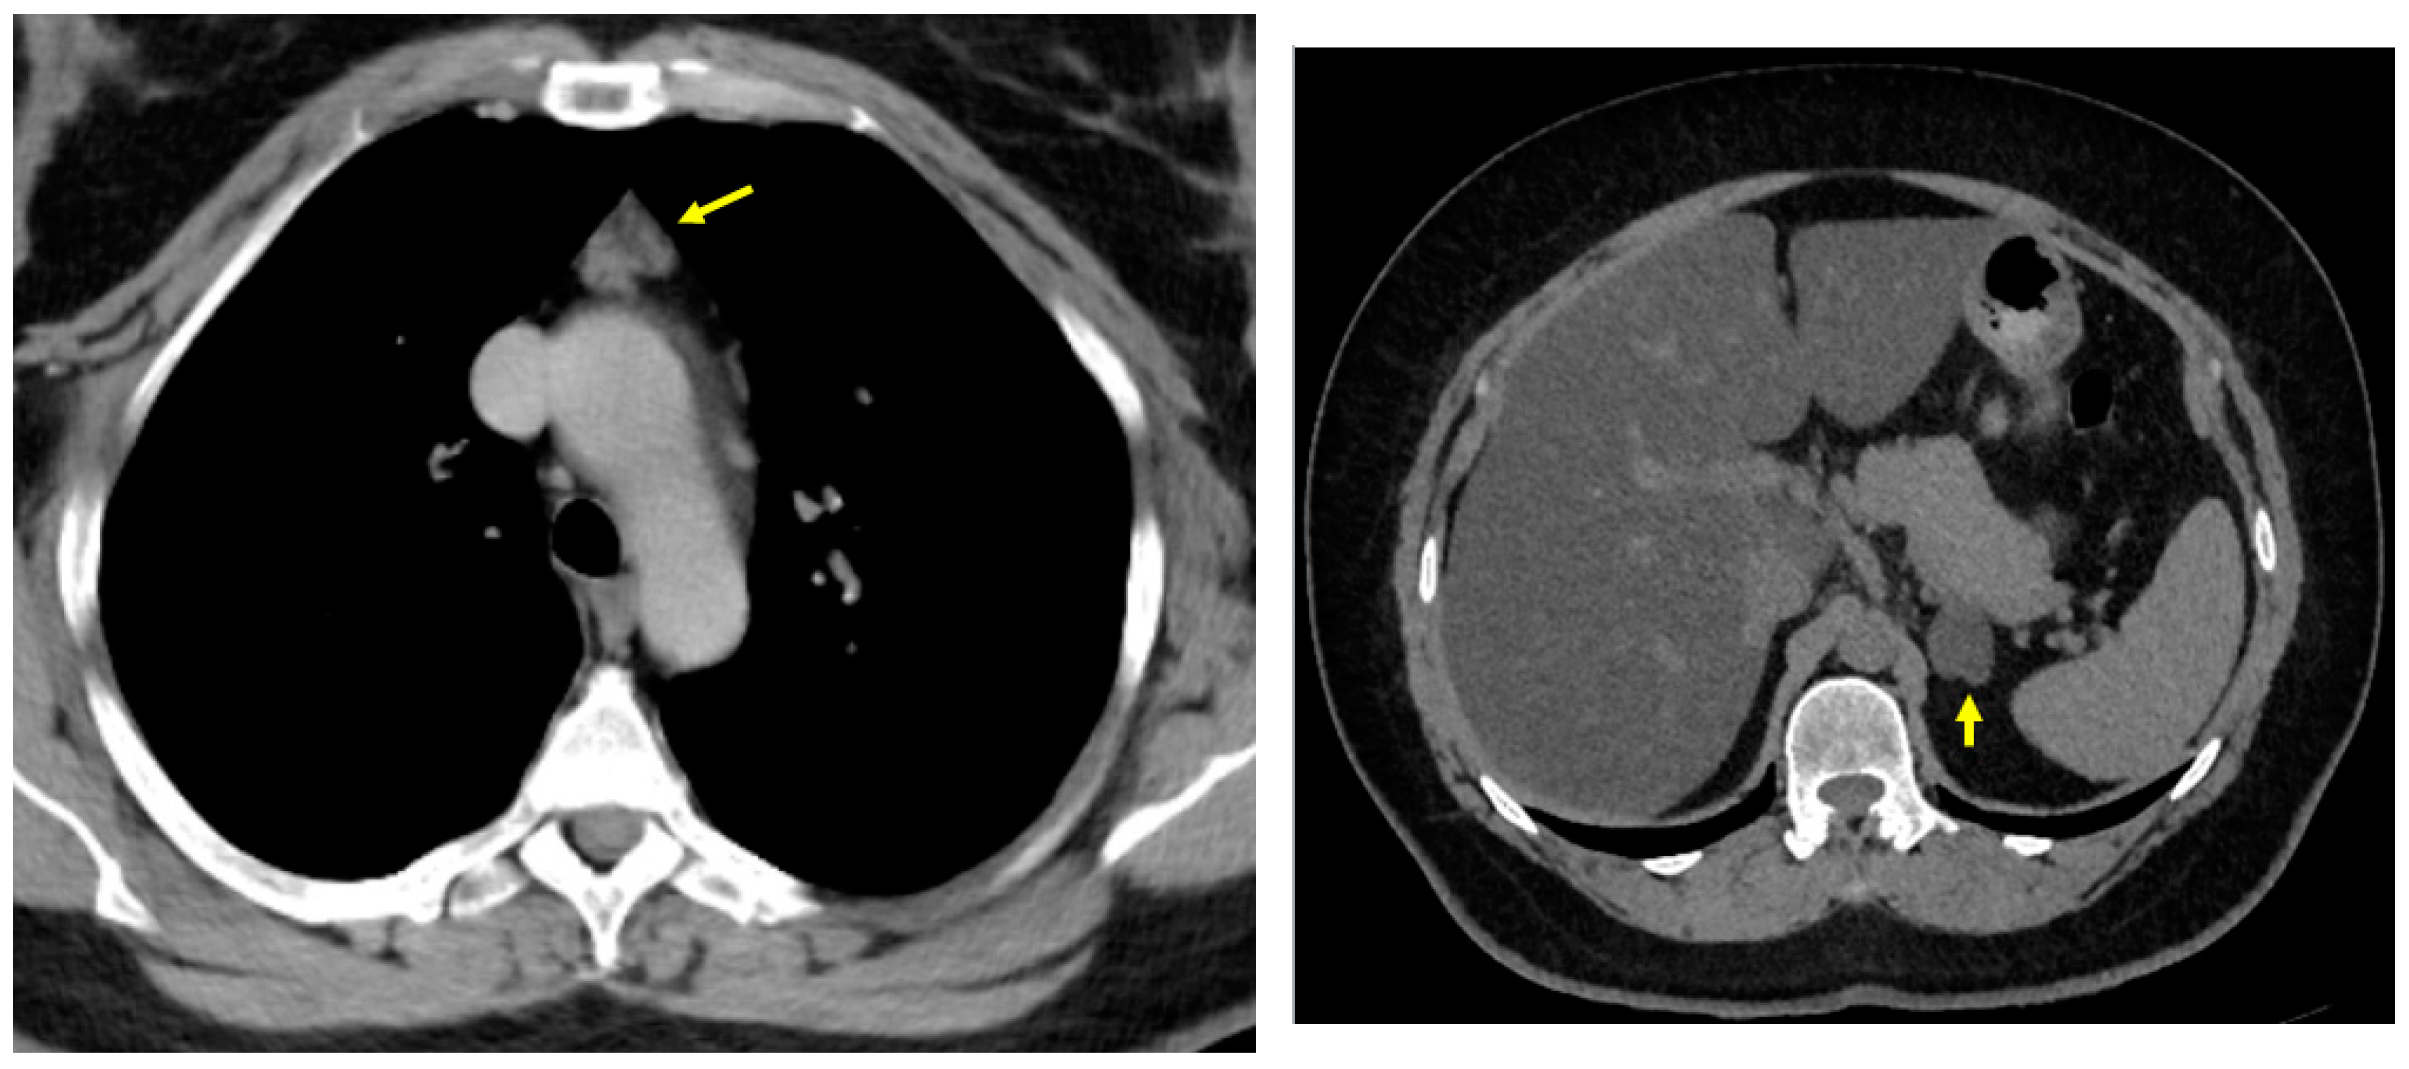

3.1.1. Baseline Admission: Identification of a Mediastinal Mass and an Adrenal Tumour Following Prior COVID-19 Infection

3.1.2. Endocrine and Imaging Investigations After One Year of Surveillance

- At the initial computed tomography, a small line of tissue was suspected to be the connective tissue between the orthotopic and ectopic thyroid, but it was not intra-operatory confirmed or after the post-surgery histological exam. This connective tissue facilitates the distinction between ectopic mediastinal tissue and a retrosternal extension of a cervical goitre [79];